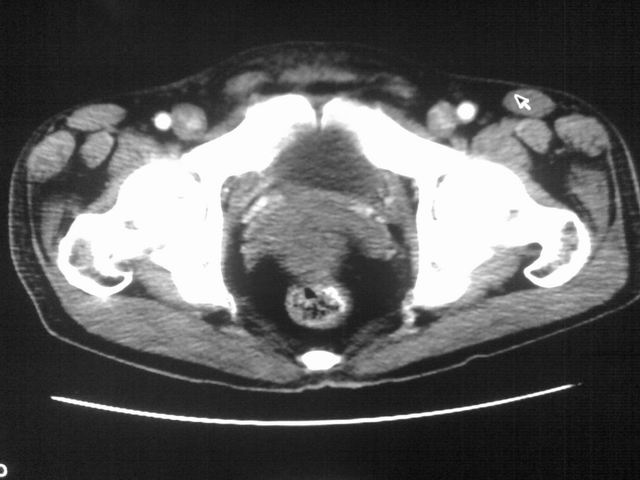

患者m 56岁,盆腔及下腹部胀痛半年,加重1月余,消瘦\中重度贫血.(附:平扫时直肠的高信号为,残留的钡剂).补一下病史:胃镜及纤维结肠镜均无明显异常.

首先是病灶的定位,平扫看很象肠管肿瘤但既然纤维结肠镜正常就可以除外结肠病变,增强成不均匀强化,位于右下腹部应该首先考虑回肠末段占位性病变,1淋巴瘤,2间质瘤,3腹膜后神经原肿瘤待除外,

膀胱后方及直肠前方见巨大混杂密度影,与前列腺相连且向膀胱内突入,精囊腺显示不清;考虑前列腺癌侵犯精囊、膀胱。

膀胱及直肠间有不规侧的软组织密度影,内密度不均匀。其内有坏死囊变,前列腺及精囊腺,膀胱后壁受浸。结合病史考虑腹膜后肉瘤可能性大。